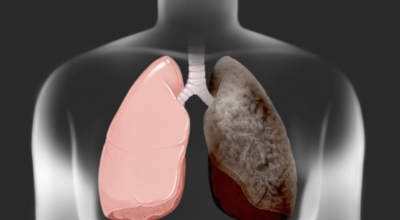

폐암 원인

폐암의 가장 큰 원인이며, 폐암 환자의 80-90%가 흡연에서 비롯될 수 있다고 할 수 있어요. 흡연을 자주 할 시 폐암 발생 위험이 흡연을 하지 않은 사람보다 13배가 증가를 할 수가 있고, 간접흡연 역시 1.5배나 폐암 걸릴 확률이 있어 흡연은 폐암 그 자체라고 생각하시면 될 것 같아요.

가족력으로 폐암에 걸릴 수가 있어요. 친척 포함 가족력 역시 폐암을 무시할 수가 없는데 가족 중 폐암을 가지고 있는 사람이 있을 경우 2~3배 발병률이 높는 것으로 알려져 있어요. 마지막은 생활환경이지요. 흡연 외에도 가스, 미세먼지, 암 유발 물질 노출, 대기오염 과 같은 생활환경에 따라 폐암이 발생할 수 있어요.